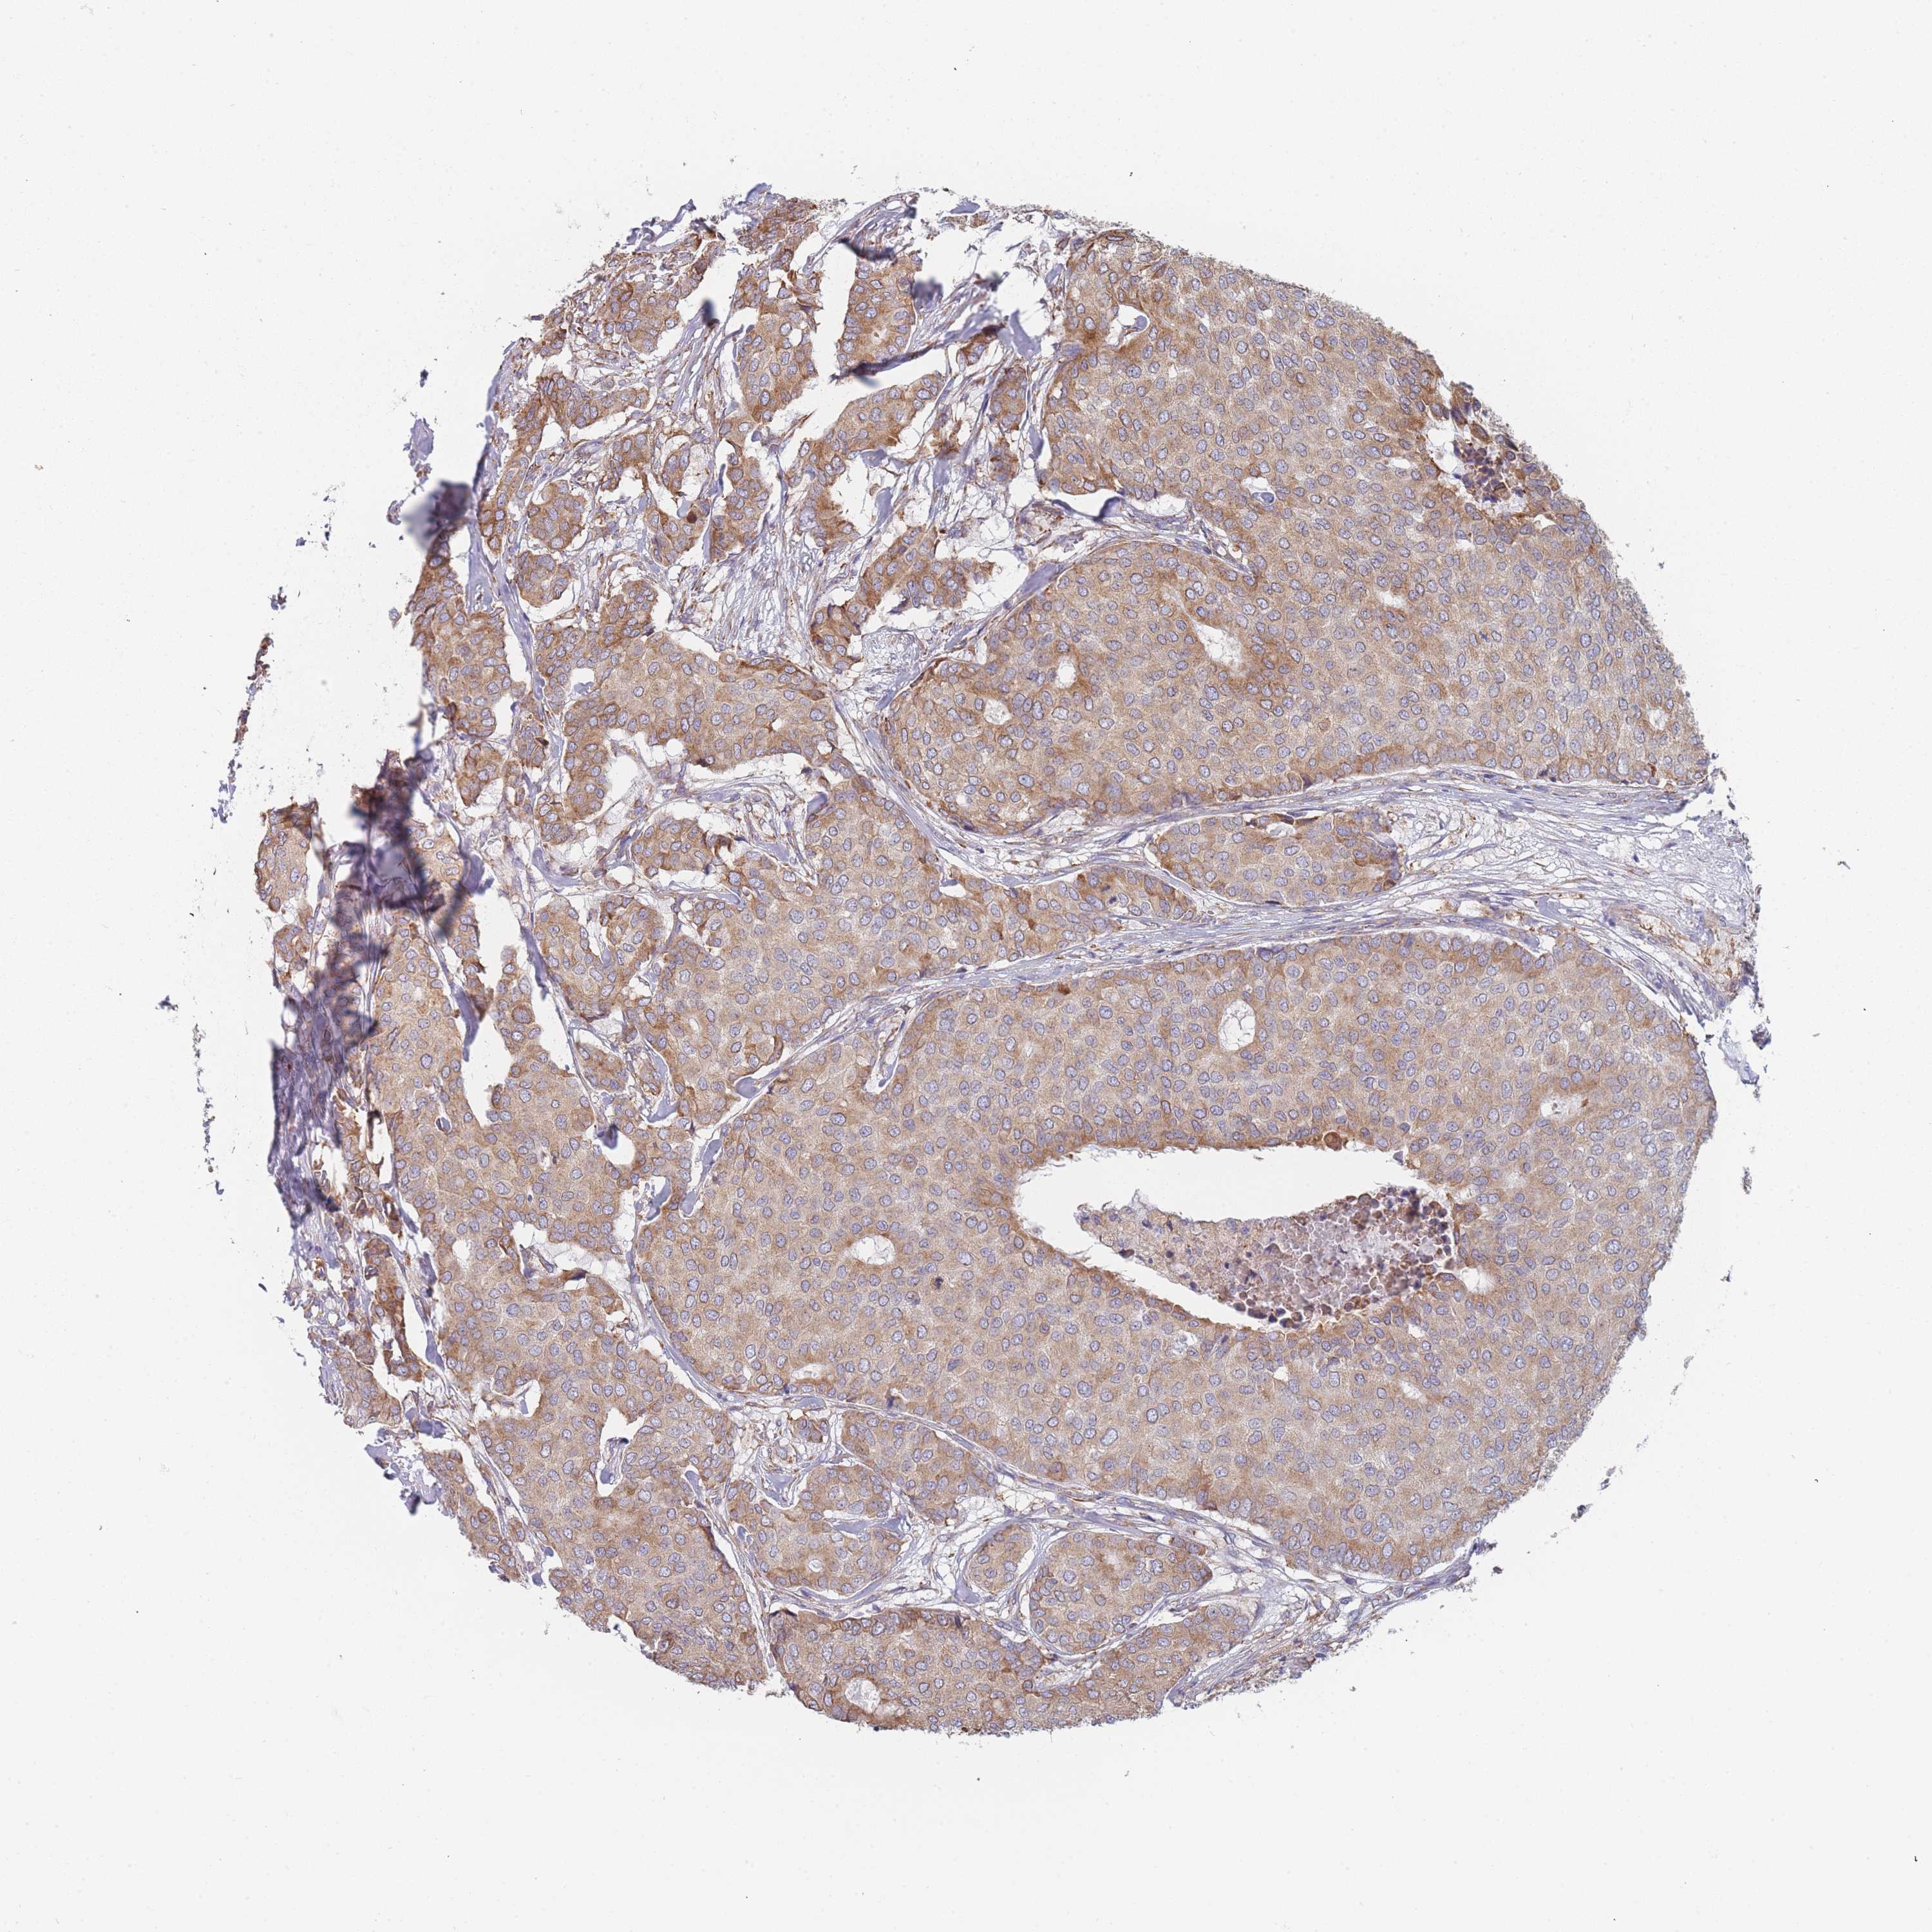

CANCER BREAST CANCER Show tissue menu

Breast cancer

Human cancer